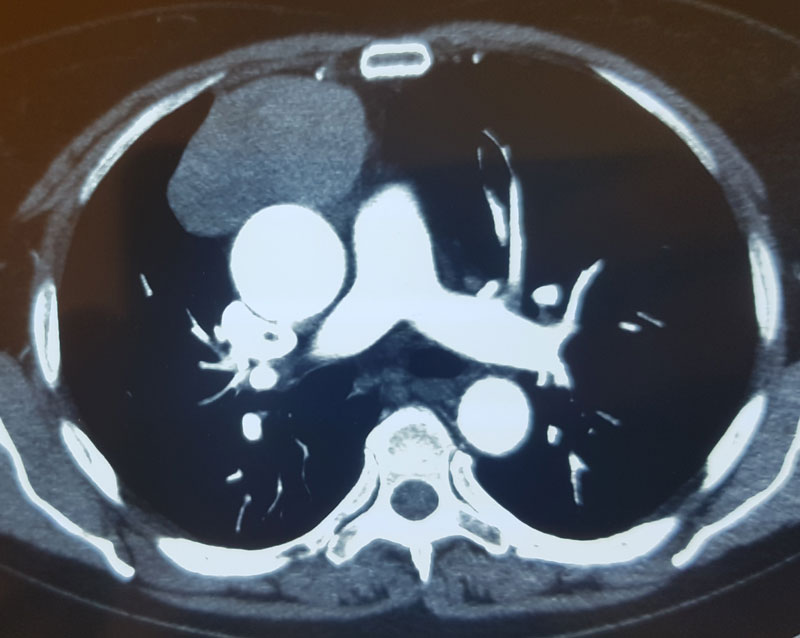

В Клинике грудной и сердечно-сосудистой хирургии им. Святого Георгия начато выполнение операций аортокоронарного шунтирования с применением методики ЮрЛеон и с использованием Левосимендана у больных ИБС со сниженной фракцией выброса.

В Пироговском Центре проведена уникальная успешная операция по удалению опухоли правого предсердия с остановкой сердца на 3 минуты без подключения к аппарату искусственного кровообращения

В Пироговском Центре проведена уникальная успешная кардиохирургическая операция на открытом сердце без подключения к аппарату искусственного кровообращения

Первая робот-ассистированная операция на сердце — аортокоронарное шунтирование

Пройден этап 1 000 операций на сердце

В короткий срок с момента образования Пироговского Центра, в клиническую практику были внедрен весь спектр современных хирургических вмешательств. Применяются как мининвазивные технологии, так и традиционные операции.